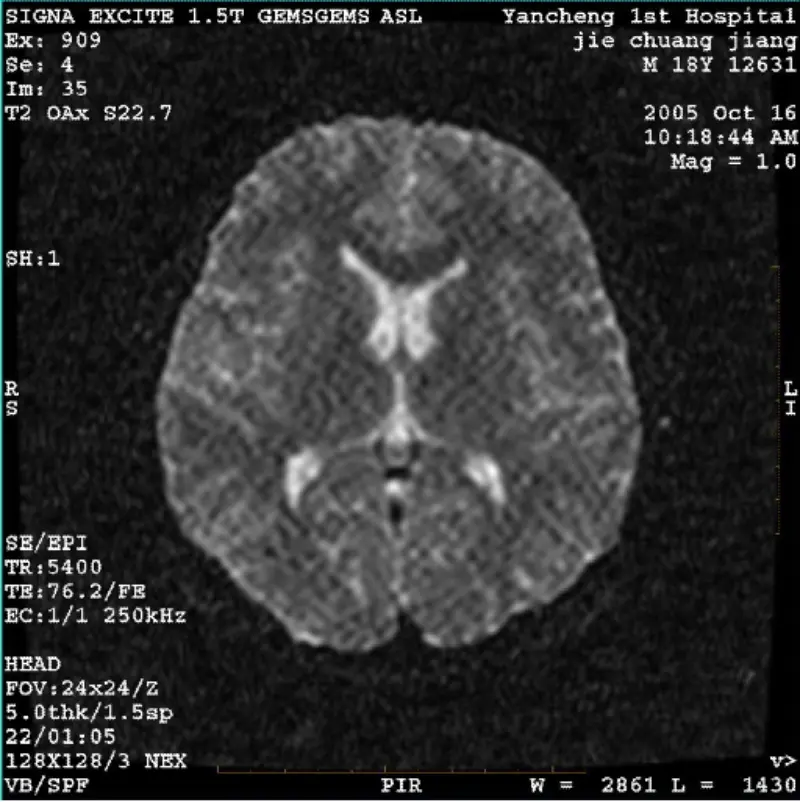

더 읽어보기SYSTEM: MR 0.35T Ovation Hospital: Daqing Oilfield General hospital PROBLEM/SYMPTOM The images of FRFSE and GRE protocols has ghost and sometimes low SNR SYSTEM: MR 0.35T Ovation Hospital: Daqing Oilfield General hospital PROBLEM/SYMPTOM The images of FRFSE and GRE protocols has ghost an......